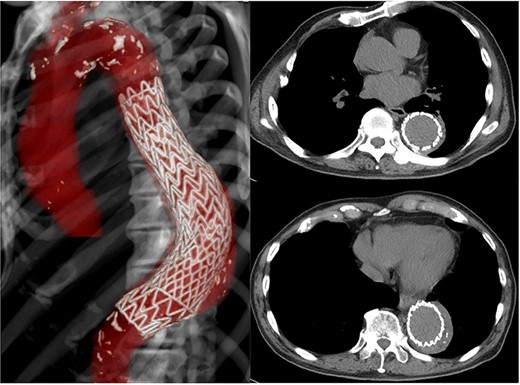

The patient had no back pain when he came to our hospital. His laboratory data on admission indicated severe infection, i.e. a white blood cell count of 15 080 cells/μL and C-reactive protein of 24.9 mg/dL. CT angiography showed an aneurysm, measuring 50 × 57 mm, with an effusion around it (Fig. 1). Because a mycotic aortic aneurysm was strongly suspected, intravenous antibiotic therapy was started with tazobactam/piperacillin hydrate, despite negative blood cultures.

CT shows a descending aortic aneurysm (a), 50 mm in diameter (b), surrounded by an effusion (c).